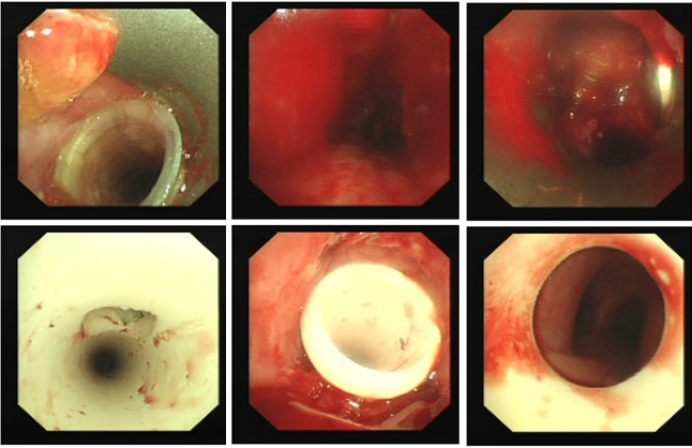

病例2

患者为77岁女性,有气管插管20余天拔管史,因呼吸困难2个月、加重3天入院。入院时(12月2日):心率125次/分,呼吸30次/分,静息下SpO2 96%(高流量,FiO2 30%),PaCO2 56 mmHg;12月3日病情恶化,心率140次/分,呼吸35次/分,血压190/90 mmHg,SpO2  68%~75%(FiO2 100%),躁动不安。紧急床旁气管镜检查见气管中下段狭窄85%以上,狭窄口有黄白黏稠分泌物随呼吸摆动,予以抽吸后SpO2升至98%。10#球囊多次扩狭窄部位增宽。后成功置入气管导管,氧合指数300 mmHg以上。后续复查气管镜,多次行球囊(12#)扩张、冷冻消融清除坏死物及局部激素灌注治疗,12月5日拔除气管导管,12月14日病情稳定出院。

图片

3  球囊扩张治疗